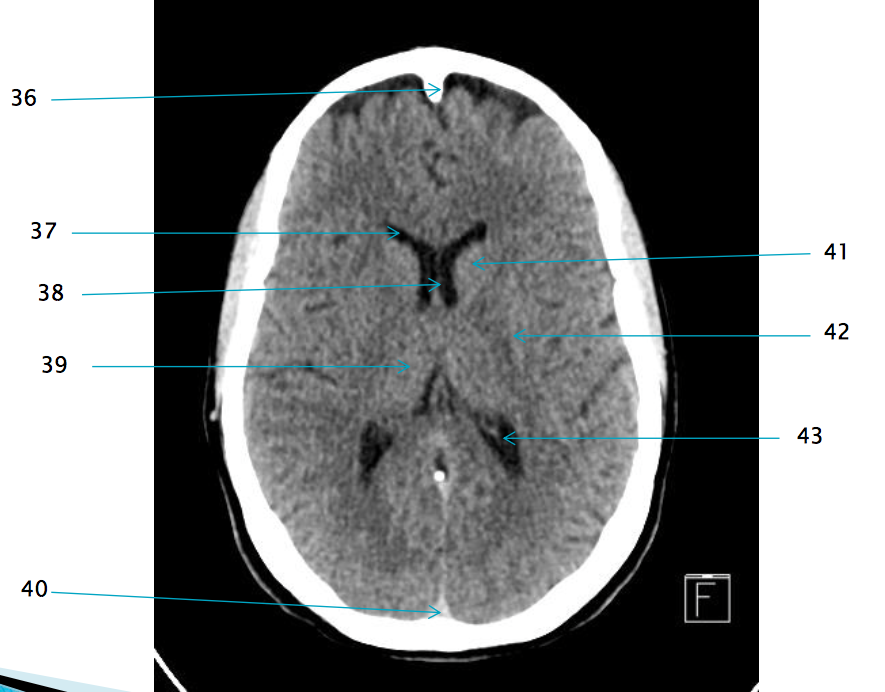

35

Superior sagittal sinus

37

Frontal horn of R lateral ventricle

38

Septum pellucidum

32

R frontal lobe